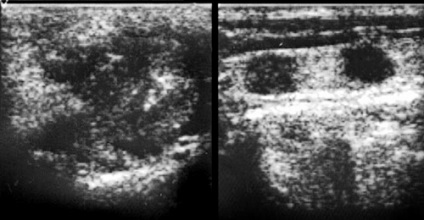

A gyulladásos betegségek, a mirigyeket echography lehetővé teszi a differenciál diagnosztikájában különböző formáinak mumpsz, azonosítani angiosialitis - gyulladás a csövekben a nyálmirigyek, a gyulladás felismerik vnutrizhelezistyh nyirokcsomók (nyirokcsomó), és hogy tisztázza a szakaszban. Mindez lényegében egy differenciálódását sebészeti és nem sebészeti patológiai a mirigyeket (ábra. 1-7).

Ábra. 1. jobb oldali akut mumpsz.